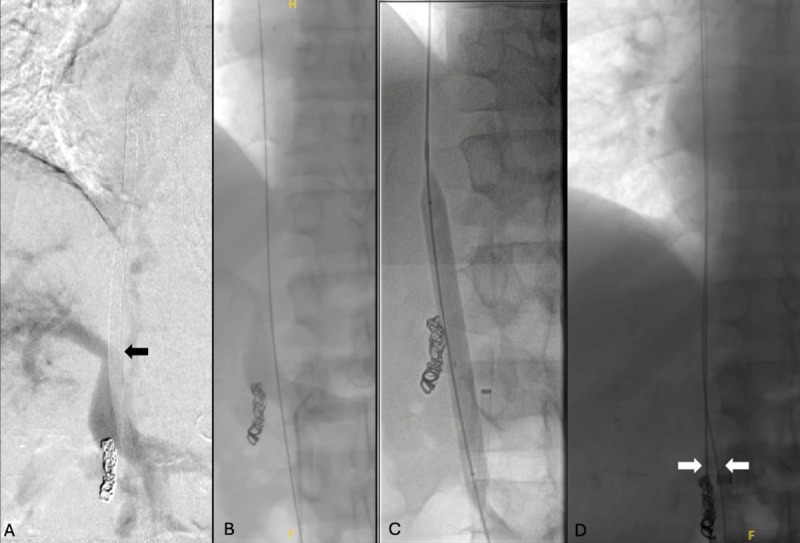

本病例描述了Merit Medical在闭塞的下腔静脉中使用Surfacer®Inside-Out Access Catheter System (SIO)。该手术通常采用右股静脉入路,有急性髂腔血栓形成的禁忌症,因为可能发生栓塞。在病史和影像学检查后,确定该病例的闭塞是慢性的,并决定使用留置导管进行SIO手术。本病例展示了SIO手术在已用尽所有其他选择的中心静脉闭塞患者的某些情况下的应用。

This case describes the use of the Surfacer® Inside-Out Access Catheter System (SIO) from Merit Medical in an occluded inferior vena cava. The procedure typically utilizes right femoral vein access with contraindications of acute iliocaval thrombosis due to possible embolization. After history and imaging studies, the occlusion was determined to be chronic in this case, and a decision was made to employ the SIO procedure using an indwelling catheter. This case demonstrates the use of the SIO procedure in certain settings in patients with central venous occlusions who have exhausted all other options.